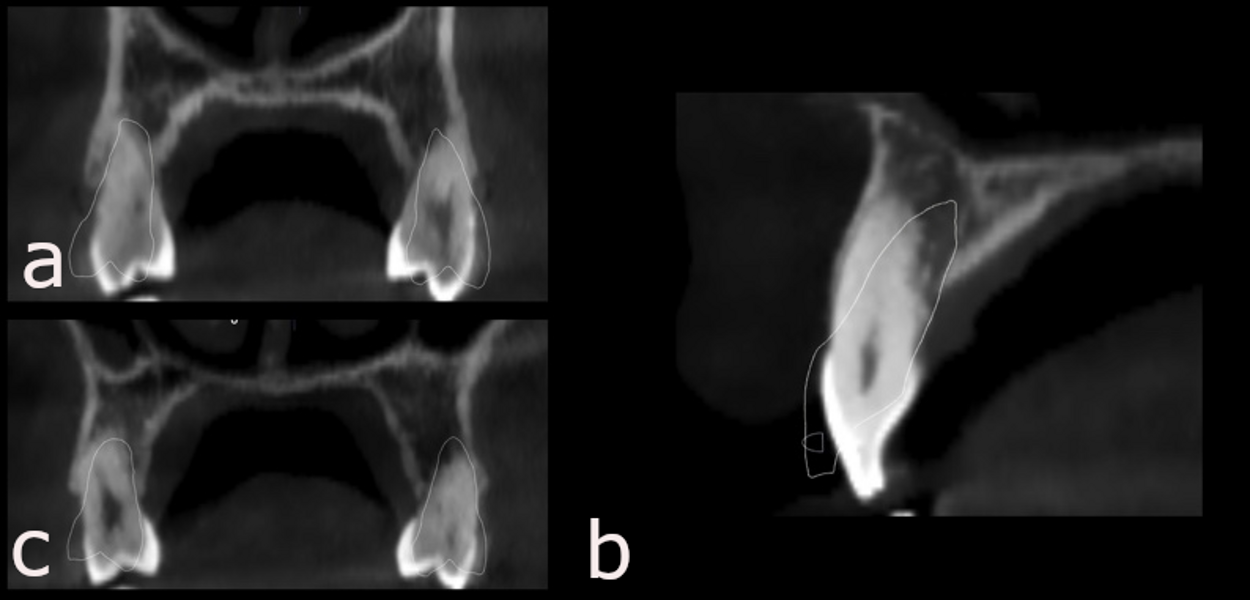

The panoramic radiograph showed slight bone loss, the presence of the maxillary third molars and mandibular left third molar and correct root morphology (Fig. 33). In the cephalometric radiograph and tracing, a Class II skeletal pattern and a marked negative torque of the maxillary incisors were observed (Fig. 34). The CBCT scan of the condyles showed that both condyles were well corticated, although the right condyle had undergone a process of PCR with reparation, evident from the good corticalisation and osteophyte (Fig. 35). This resorption process had affected the ramus, the right mandibular ramus being shorter than the left. This perfectly explained the reason for the patient’s mandibular deviation. We also observed a lack of functional space around the right condylar head, which was a clear sign that there was probably no disc present.